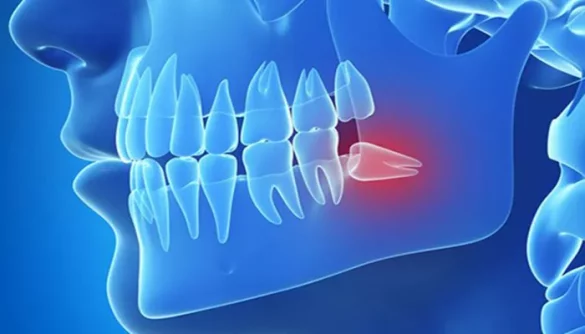

Wisdom tooth pain is a common dental problem. It usually starts between ages 17 and 25. These third molars often do not have enough space to grow. When they come in crooked or get stuck, they can cause pressure, swelling, and pain. This is called impaction.

Other causes include gum inflammation, infection, cavities, and pressure on nearby teeth. Sometimes, a wisdom tooth breaks through only partway. This makes it easy for food and bacteria to collect. The result can be pain, gum disease, or even jaw stiffness.